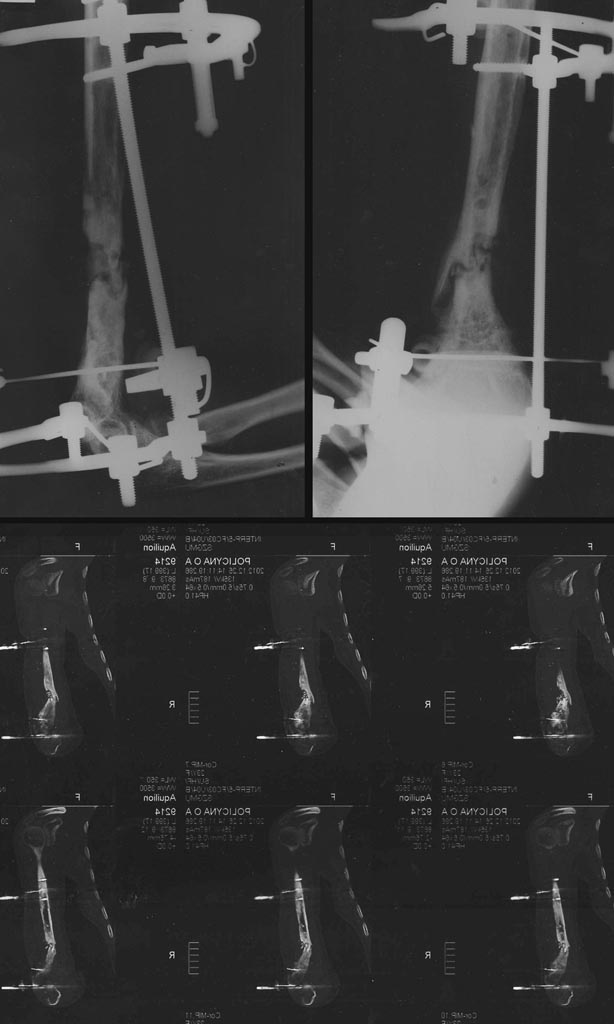

з/п левой плечевой кости. автотравма произошла 1год 9месяцев назад. За это время 4 операции.

На данный момент - ложный сустав, у одной из спиц периодически отделяется экссудат.Как лечиться дальше??